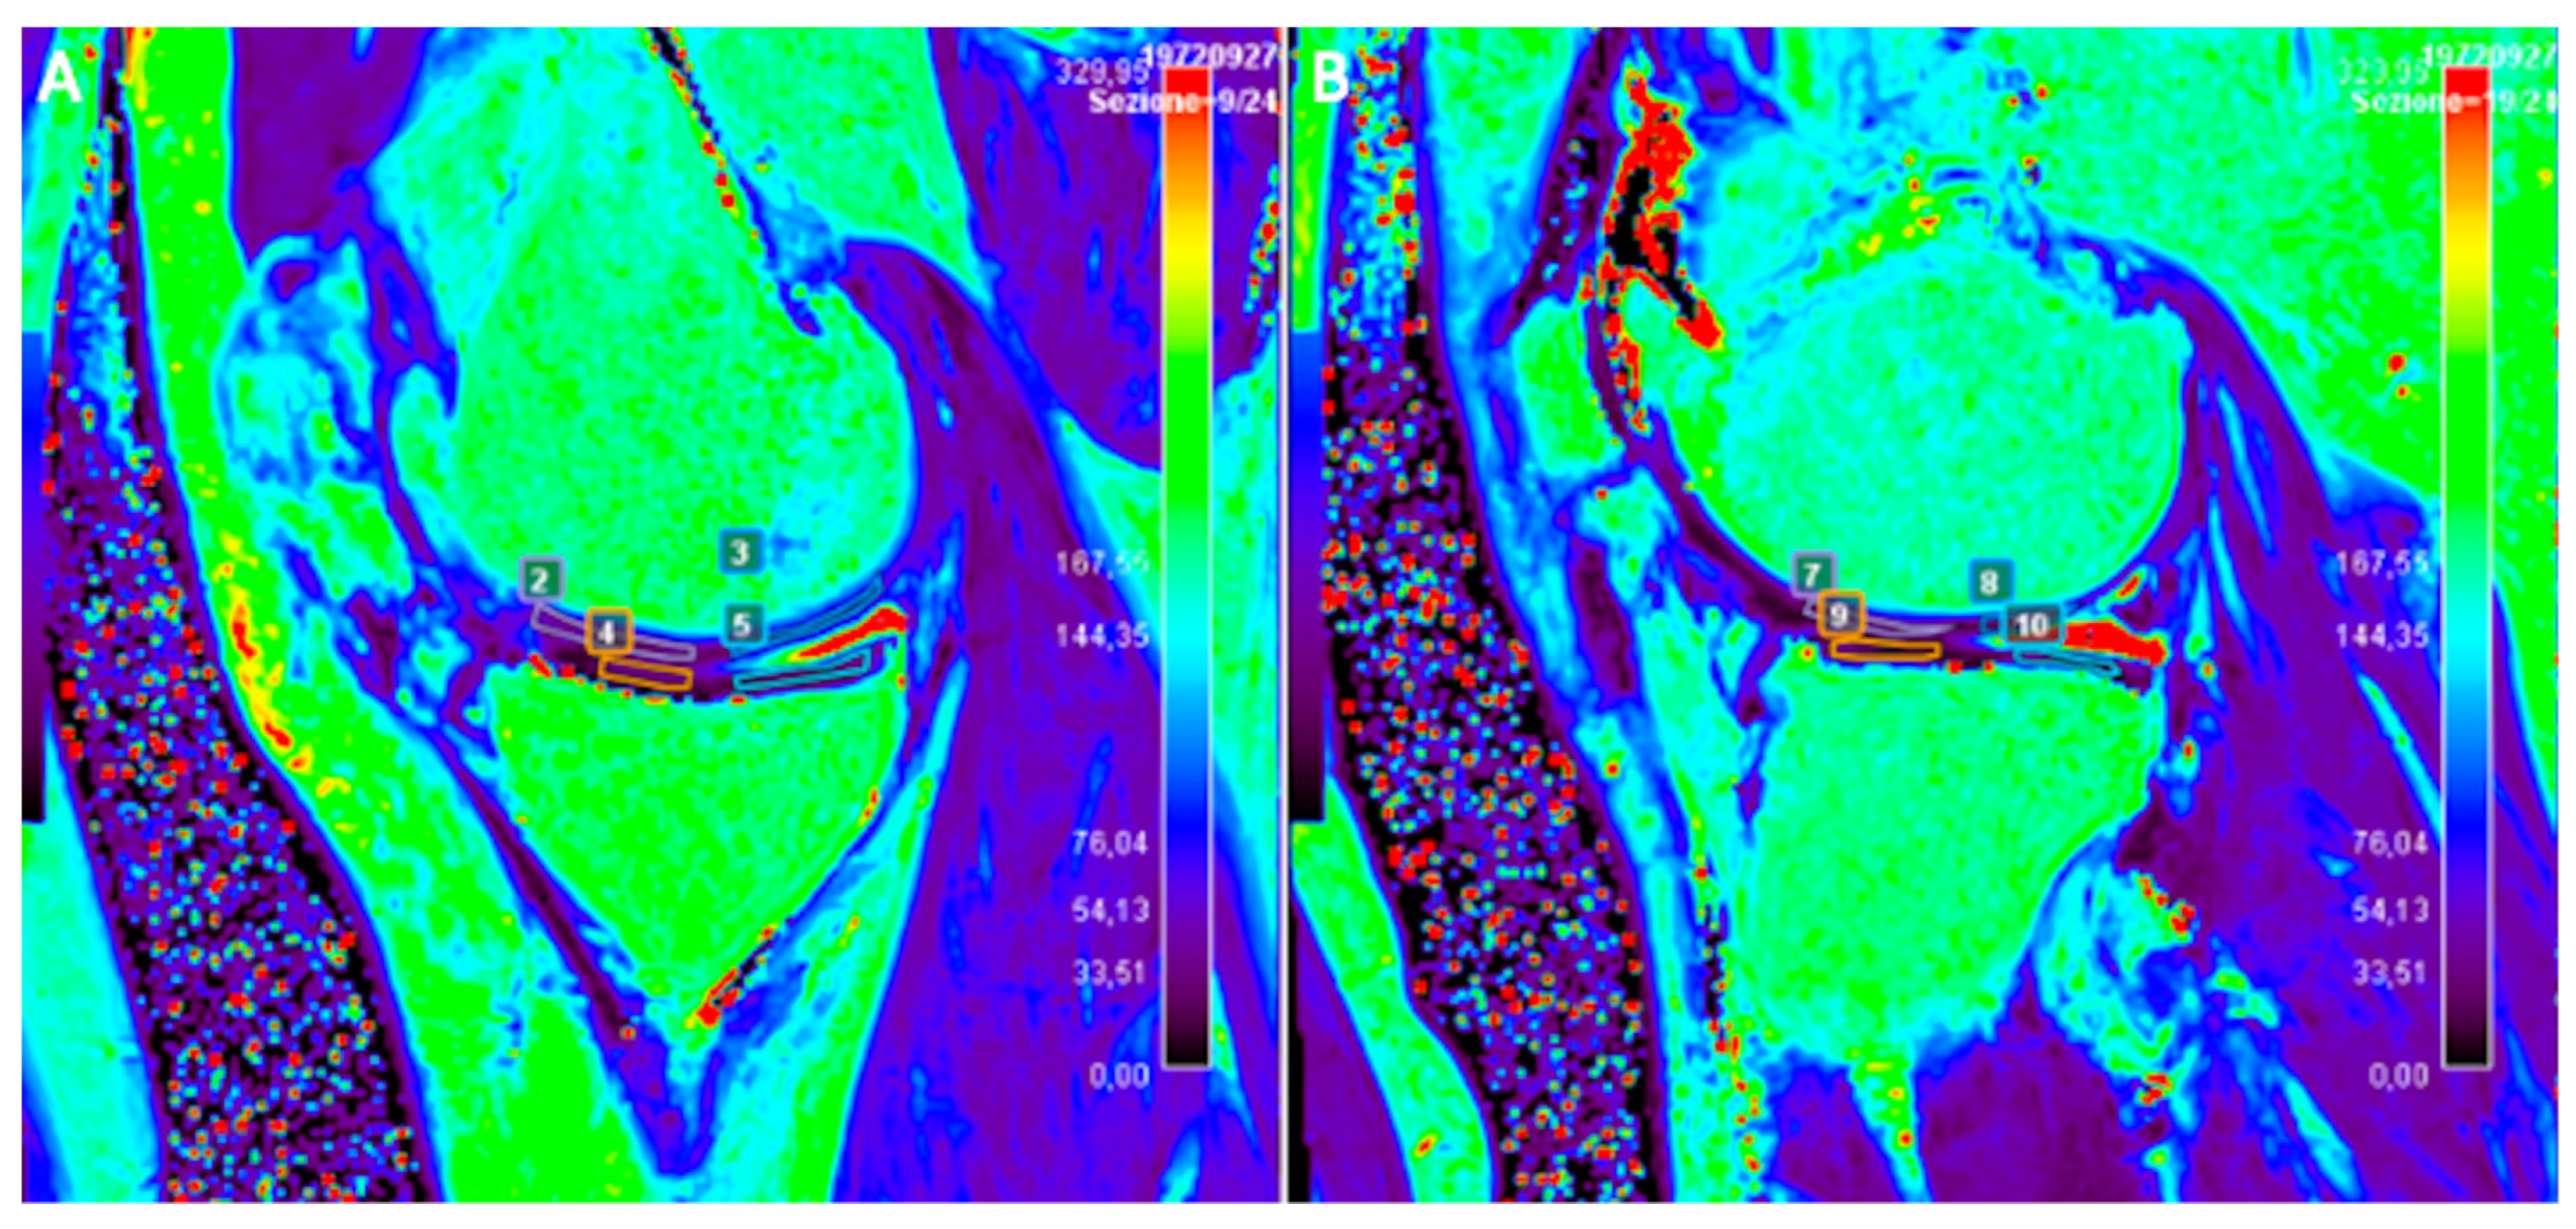

2.5. T2-Mapping

- Chianca, V.; Albano, D.; Cuocolo, R.; Messina, C.; Gitto, S.; Brunetti, A.; Sconfienza, L.M. T2 mapping of the trapeziometacarpal joint and triangular fibrocartilage complex: A feasibility and reproducibility study at 1.5 T. Radiol. Med. 2019, 125, 306–312. [Google Scholar] [CrossRef] [PubMed]

- Albano, D.; Chianca, V.; Cuocolo, R.; Bignone, R.; Ciccia, F.; Sconfienza, L.M.; Midiri, M.; Brunetti, A.; Lagalla, R.; Galia, M. T2-mapping of the sacroiliac joints at 1.5 Tesla: A feasibility and reproducibility study. Skelet. Radiol. 2018, 47, 1691–1696. [Google Scholar] [CrossRef] [PubMed]

- Albano, D.; Bignone, R.; Chianca, V.; Cuocolo, R.; Messina, C.; Sconfienza, L.M.; Ciccia, F.; Brunetti, A.; Midiri, M.; Galia, M. T2 mapping of the sacroiliac joints in patients with axial spondyloarthritis. Eur. J. Radiol. 2020, 131, 109246. [Google Scholar] [CrossRef] [PubMed]

| T2-mapping | T2*, UTE-T2*, T2w SE, FSE, Multi Echo SE, Turbo Gradient SE, DESS Cartilage hydratation, Cartilage, Water | High reproducibility. T2* and UTE sequences allow a better visualization of deep cartilage and osteochondral junction. Predictive for OA in areas with much compression loading. No contrast administration. | Susceptible of magic angle artifact and magnetic field inhomogeneity. |